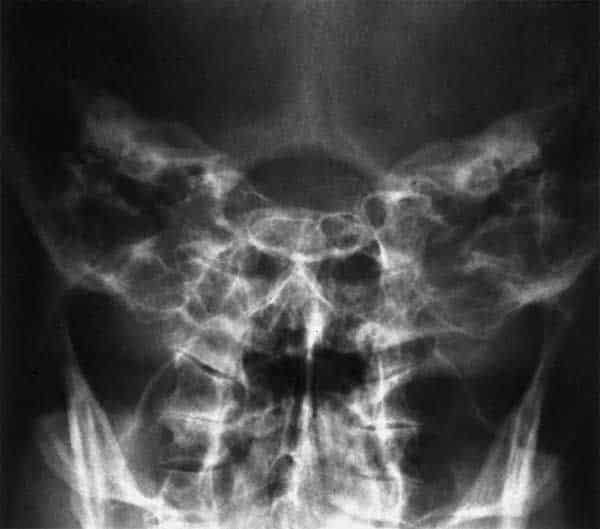

Base del cráneo y Vista de Autschul para crestas petrosas

- tabique nasal

- hueso cigomático

- pared posterior del seno maxilar

- seno maxilar (con órbita, parcialmente superpuesta)

- fosa craneal media, ala mayor (pared anterior del craneal media fosa)

- fosa pterigopalatina

- Proceso coronoides

- fosa pterigoidea

- seno esfenoidal

- Foramen ovale

- foramen espinoso

- Clivus

- Agujero rasgado

- cóndilo de la mandíbula

- Cóclea

- conducto auditivo interno

- canales semicirculares

- arco anterior del atlas

- foramen yugular

- celdas mastoideas

- odontoides

- Foramen magnum

- Columna cervical

- cresta petrosa

- eminencia Arcuata

- Vestibulo

- canal semicircular anterior

- semicircular lateral

- Antro de la mastoides

- cavidad timpánica

- Dorso de la silla turca

- seno frontal

- techo de la órbita

- tabique nasal y cavidades nasales

- seno maxilar

- arco cigomático